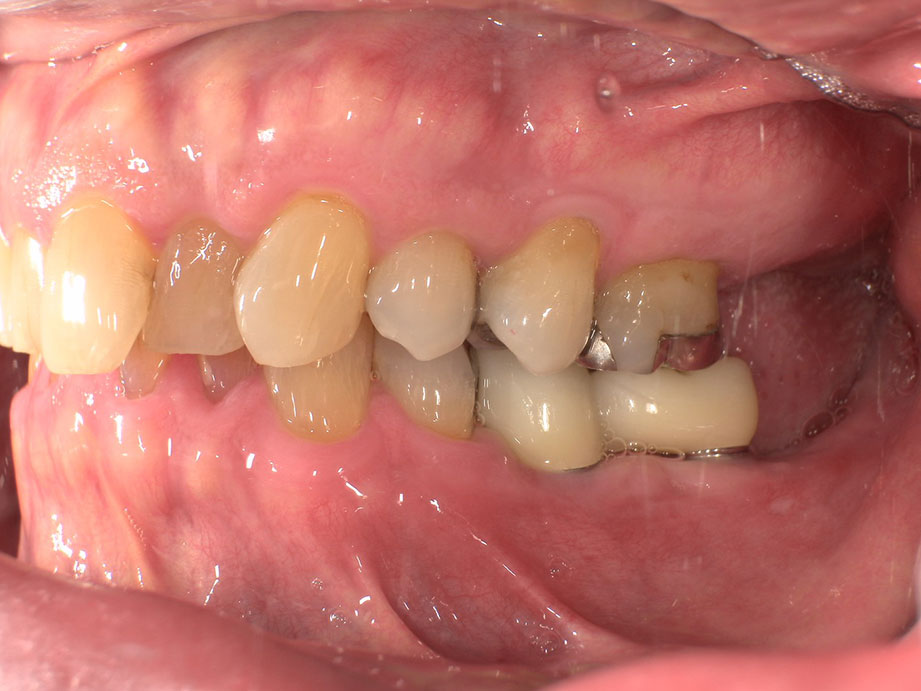

横から見た写真です。光が当たってるのでやや白く見えますが、実際はもう少し自然な仕上がりとなってます。